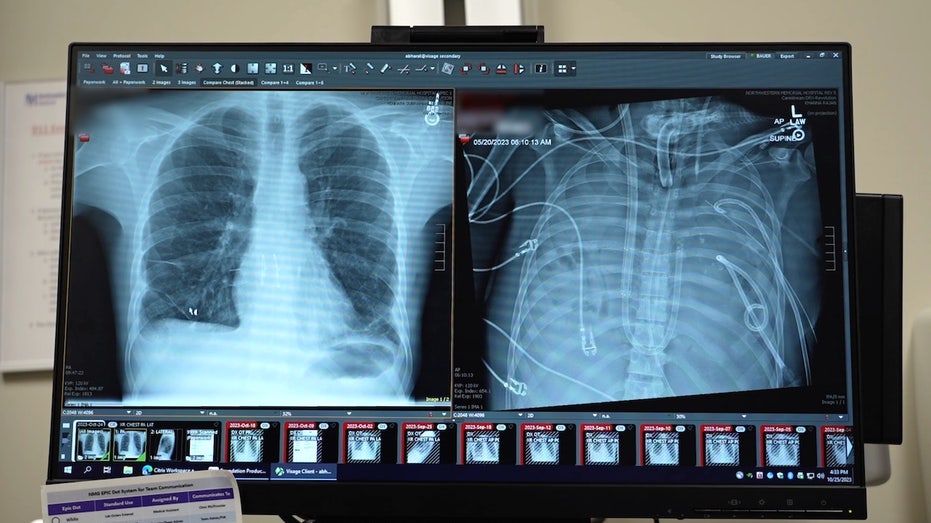

В медицинском центре Northwestern Medicine в Чикаго специалисты осуществили уникальную операцию, которая позволила сохранить жизнь 33-летнему пациенту без легких. Этот случай стал первым в мире, когда удалось поддерживать жизнедеятельность человека после удаления обоих легких с помощью специально разработанной системы искусственного дыхания.

Мужчина из Миссури был госпитализирован в Northwestern Memorial Hospital весной 2023 года с тяжелым поражением легких, вызванным гриппом. Вскоре его состояние ухудшилось: развился острый бронхит, пневмония и сепсис. В результате у пациента остановилось сердце, и врачам пришлось провести реанимацию с помощью непрерывной сердечно-легочной реанимации (CPR).

Врачам пришлось разработать уникальную систему — «полную искусственную легочную систему» (TAL), которая взяла на себя функции газообмена и поддержания кровотока, позволяя сохранить жизнеспособность пациента после удаления поврежденных легких.

Главной инновацией стала способность системы сохранять естественную физиологию сердца. Используя «адаптивный поток» (flow-adaptive design), система позволила сердцу самостоятельно регулировать кровоток, избегая вмешательства машин. Это значительно снизило риски, связанные с искусственными системами.

Через 48 часов после операции пациент был стабилен и смог пройти процедуру пересадки двойных легких. Уже через два года он вернулся к нормальной жизни и восстановил привычные функции организма.